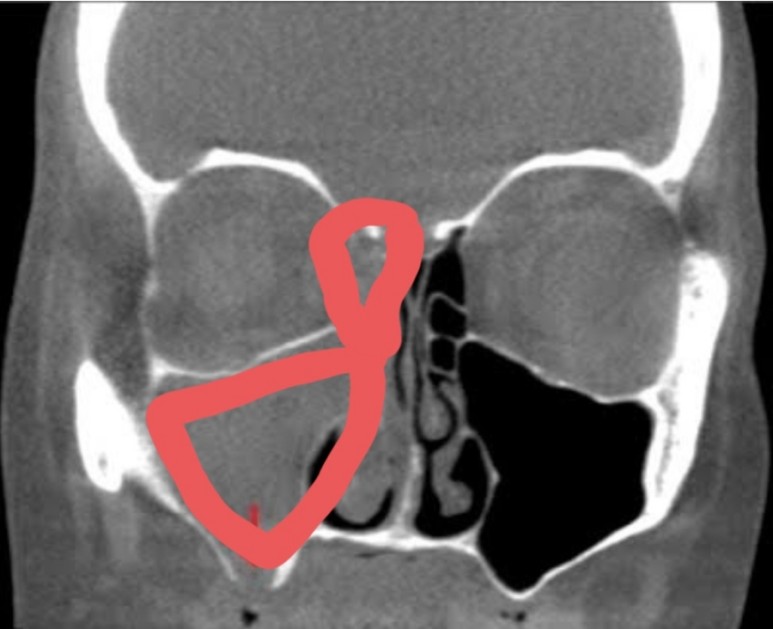

제 엑스레이는 아니지만 가능한 한 비슷한 사진을 보면 위의 사진처럼 붉은 부분이 반대쪽처럼 검게 비어 있어야 하는데 사진처럼 곪아 있더군요.

그래서인지 그 부위를 만질 때 통증도 같이 있었는데 저같은 경우에는 오른쪽 그림의 빨간색으로 체크했듯이 미간과 눈 앞 꼬리에서 눈 밑까지 누르면 상당히 아픈 통증이 있었습니다.광대뼈 아래 뺨의 부부가 누르지 않아도 뻣뻣해지는 느낌이 들었고 #관자놀이의 통증과 치통이 심했어요.